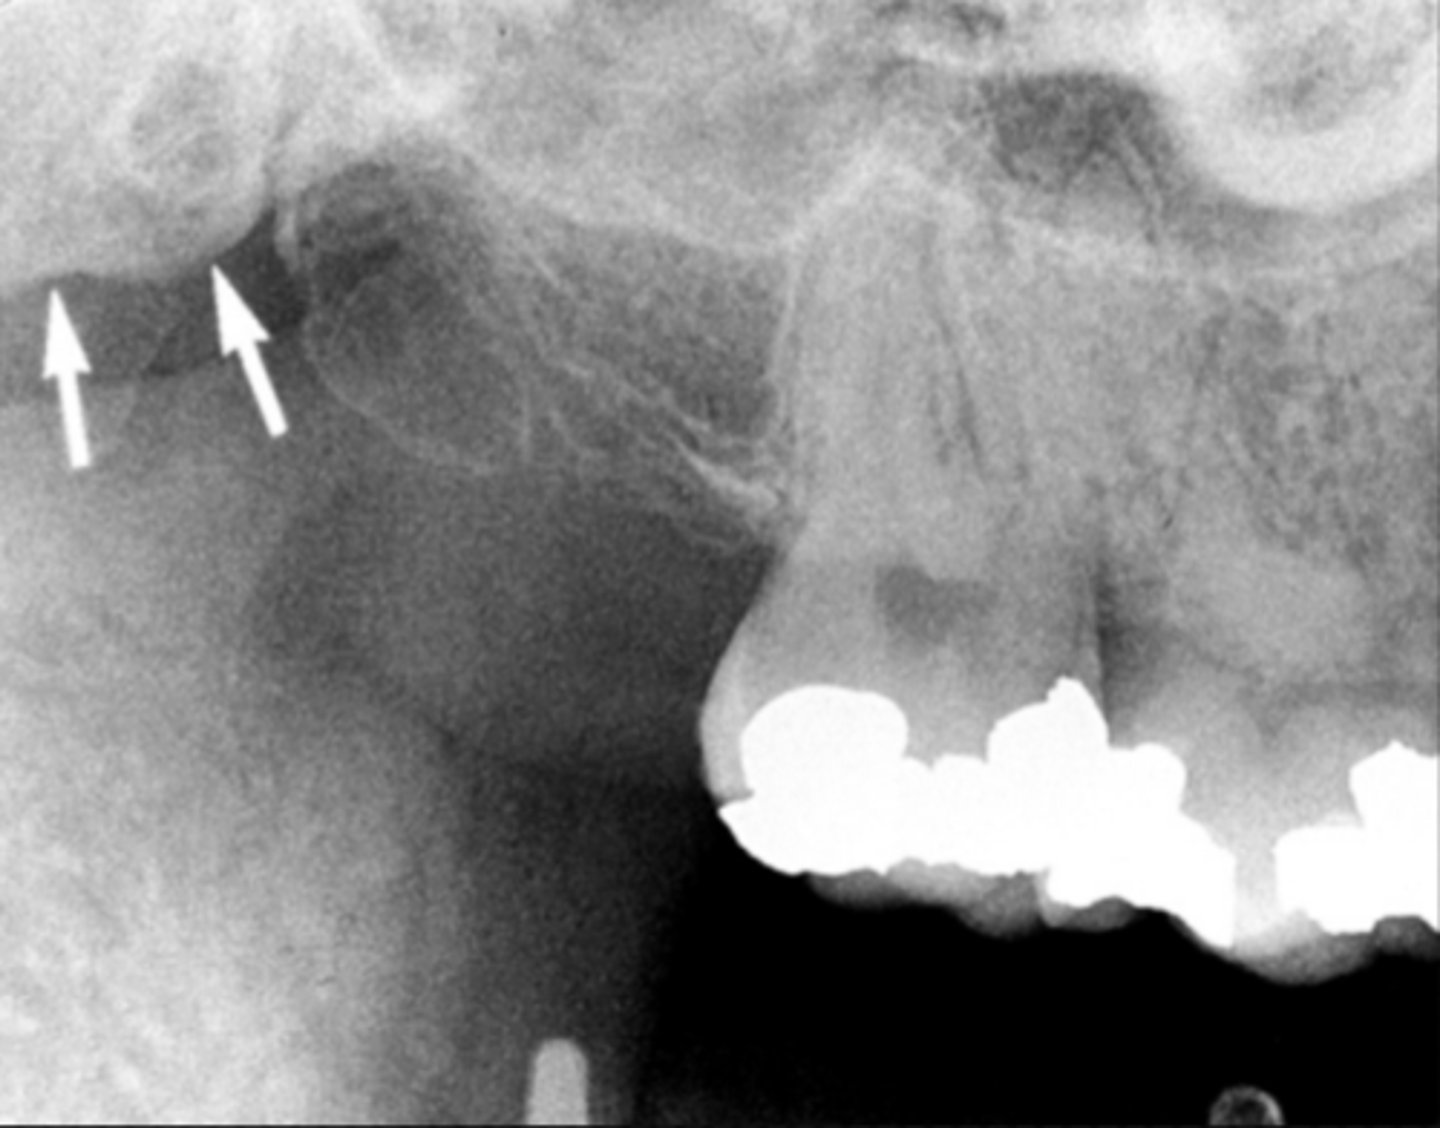

19

New cards

yellow line- zygomatic process

white arrow - zygomatic bone

Identify the two structures

<p>Identify the two structures</p>